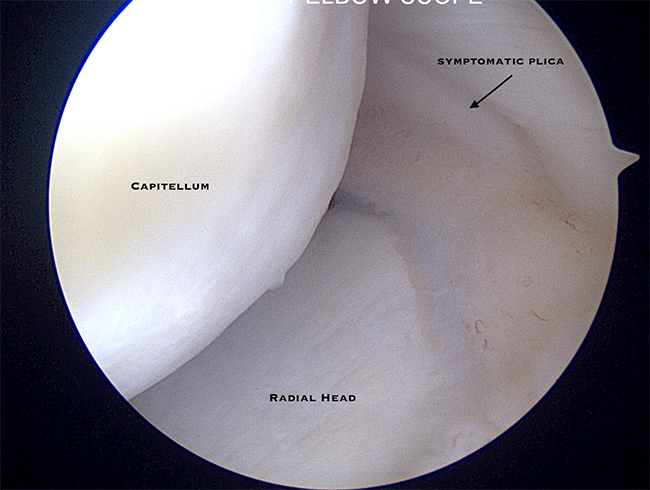

- Symptomatic Plica

- Plica is a benign thickening of the elbow capsule that can cause pain or clicking within the elbow in a select group of patients

- Symptomatic plicae are a rare cause of elbow pain in the throwing athlete

- Elbow arthroscopy allows for full assessment of the elbow and excision of symptomatic plica can be performed anthropically

Dr. Nelson performing arthroscopic excision of symptomatic plica